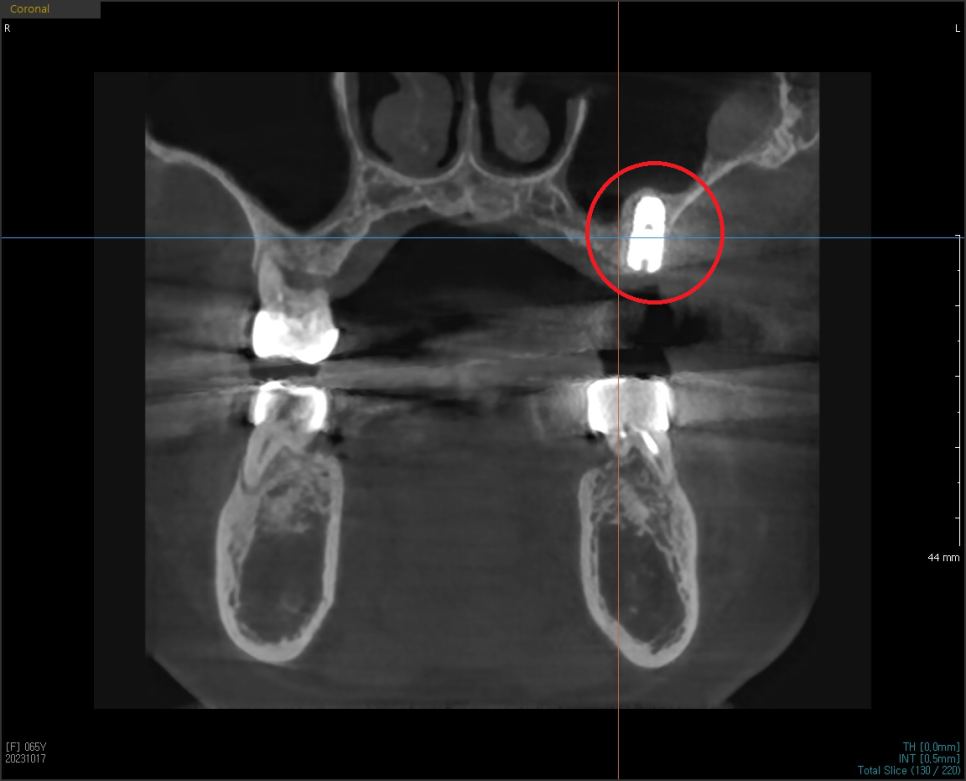

수술하기전에 삼차원 CT와 삼차원 구강 스캔 데이터를 가지고,

먼저 식립 위치를 시뮬레이션 해본 후

정확히 식립할 수 있는 네비게이션 장치를 제작합니다.

이를 맞춤장치를 제작한다고해서 "네비게이션 임플란트"라고 하는데요.

저희는 해당 디지털 기술을 적극 도입하여 뼈 상태가 좋은 자리에

정확하게 안전하게 시술하고 있습니다.

CT를 분석하여 미리 계획해둔 자리에

가이드를 장착하고 심은 덕분에

해당자리 상악동 손상없이 안전하게

상악동 거상술과 임플란트 식립을 마쳤습니다.

이번에 진행한 상악동 거상술은

상악동 수직 거상술로 수압을 이용해 막을 들어올려서

안쪽에 뼈를 채우고 해당자리에

계획한 굵기와 길이의 픽스처를 심을 수 있게 하는 방법입니다.